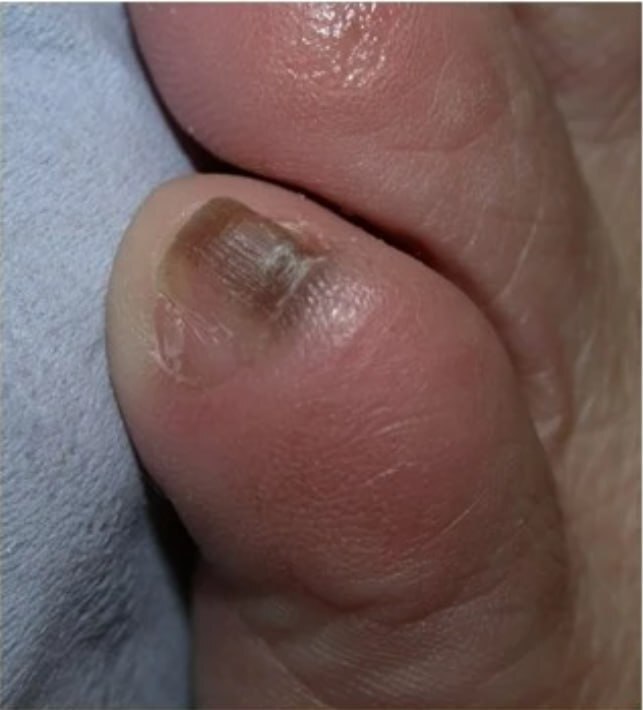

3️⃣Меланома в зоне ногтевого ложа

Коричневое окрашивание ногтя, часто в виде продольной линии всегда должно быть подозрительно на меланому, хотя может оказаться и обычным подногтевым кровоизлиянием, другими доброкачественными гиперпигментациями.